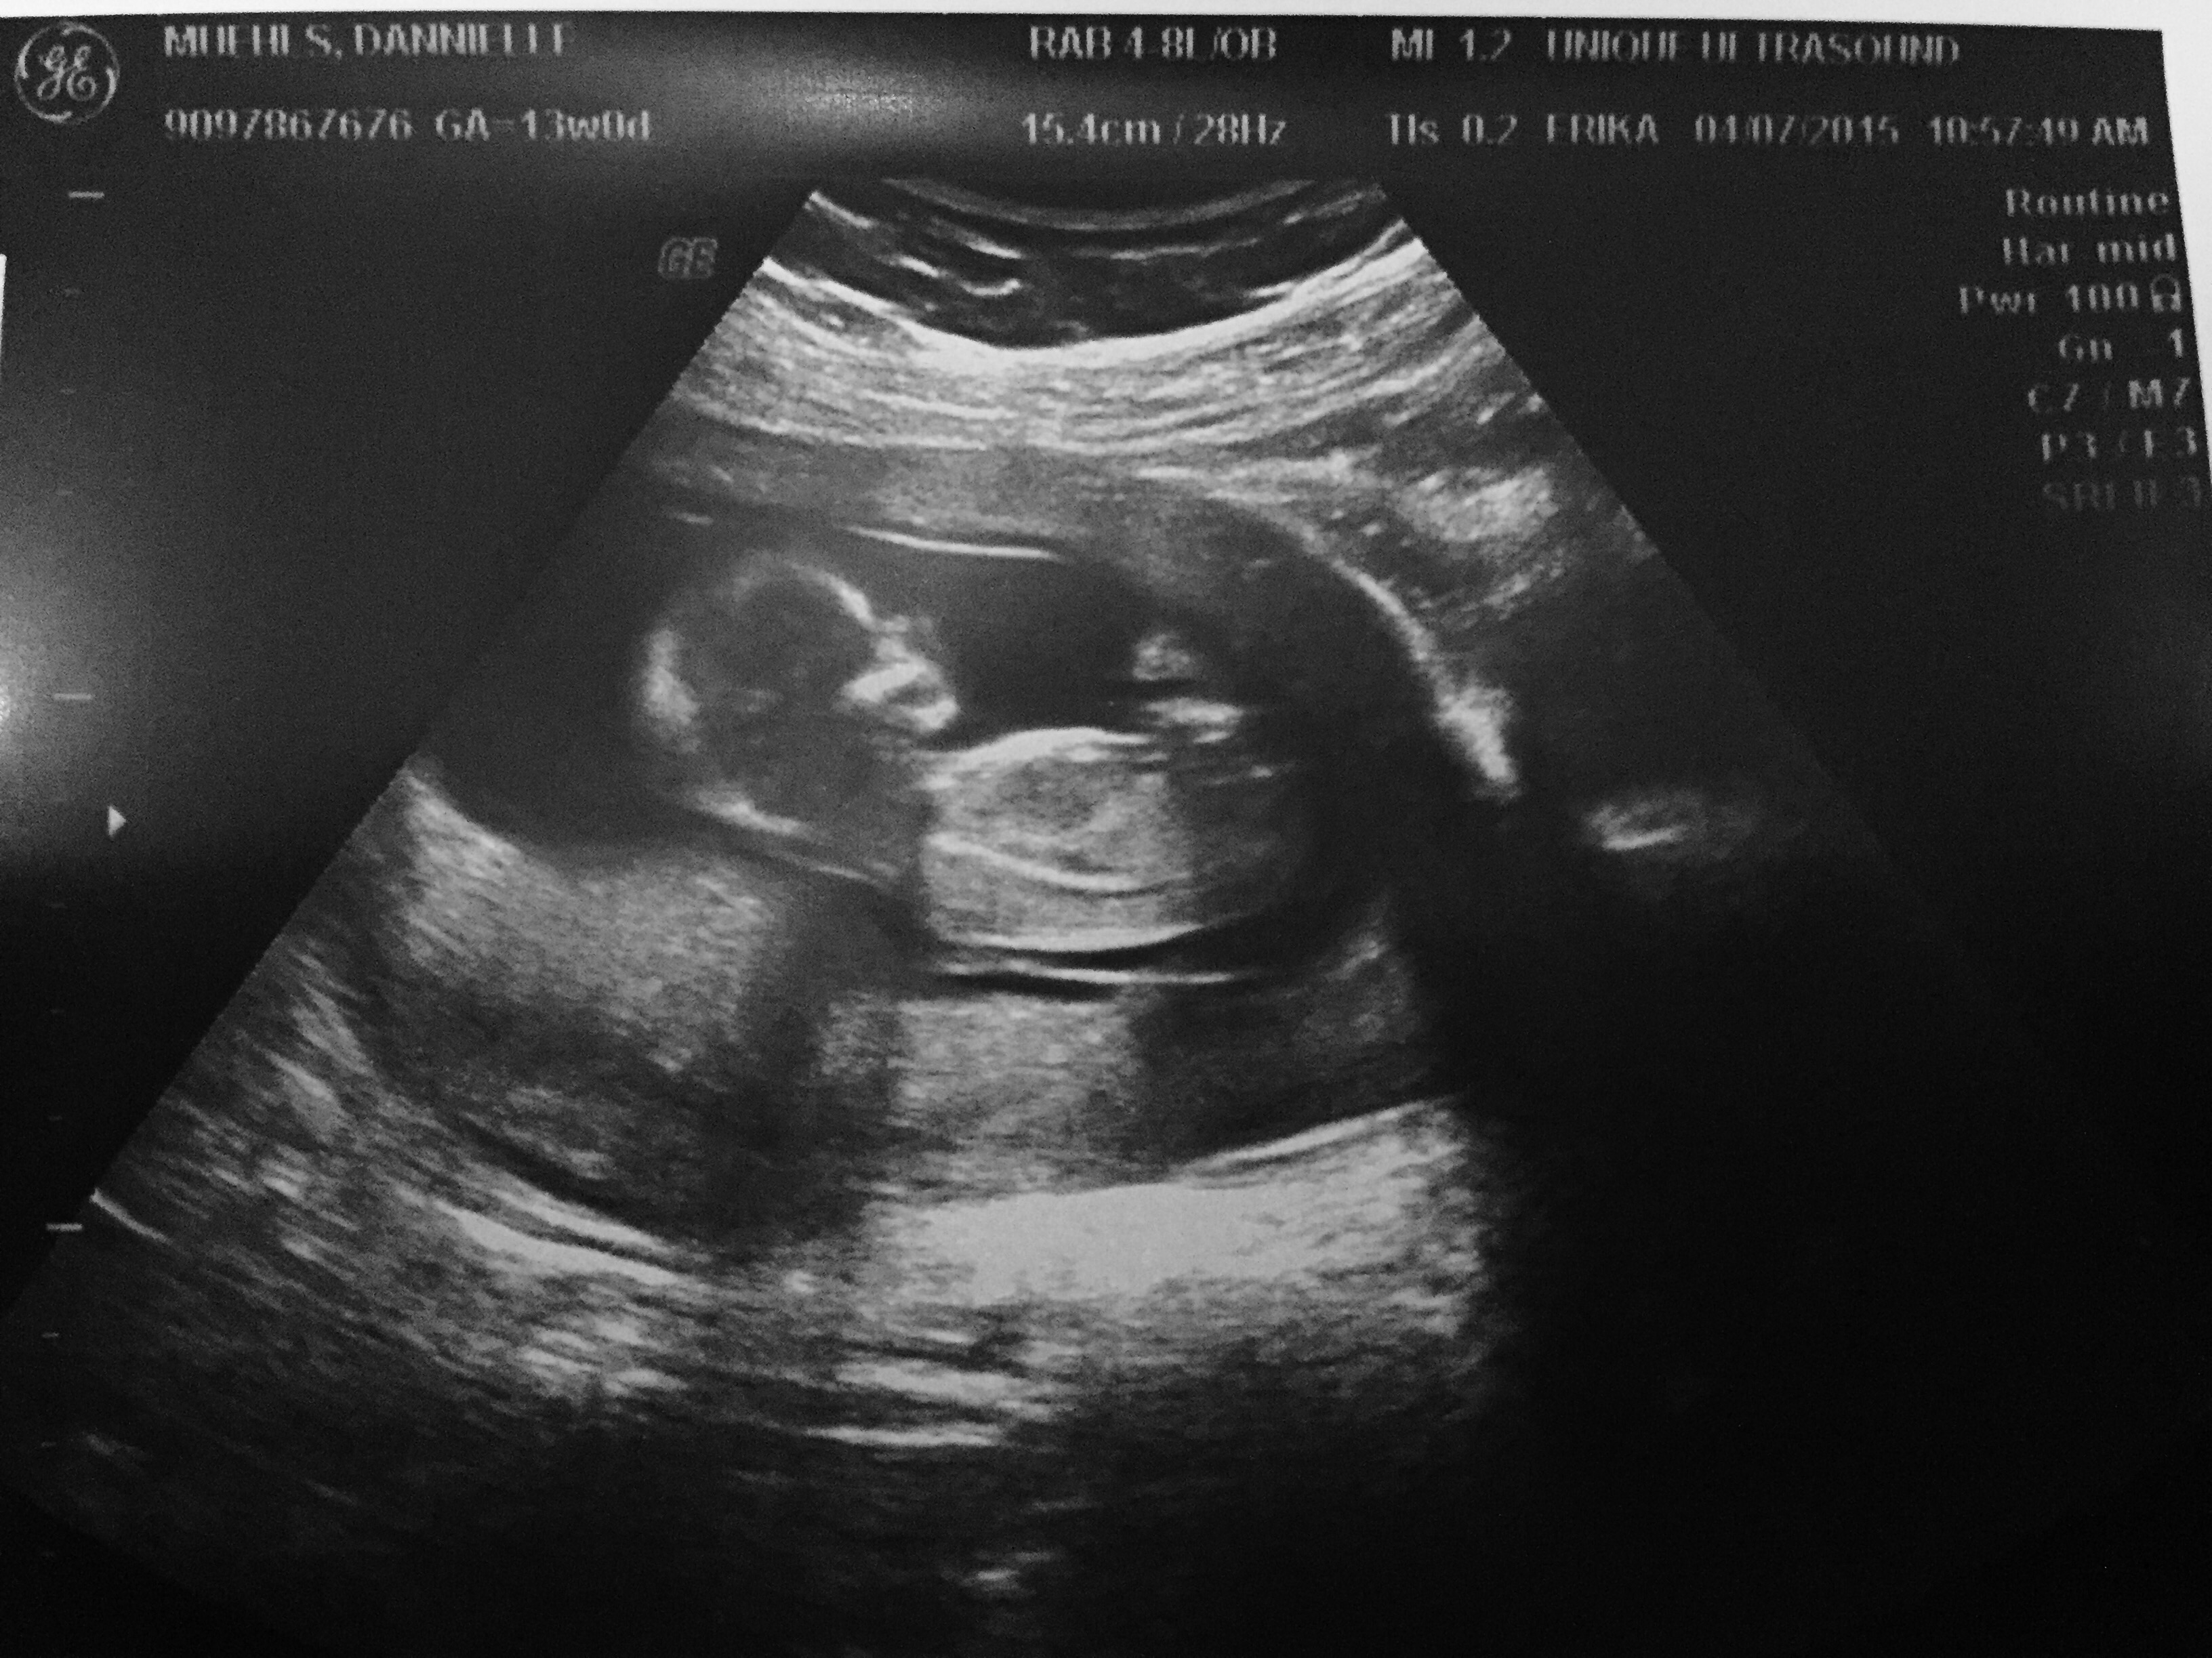

Got a surprise ultrasound today at 14w1d- thought we were just going to hear the heartbeat but we got pics too! Last time was at 9 weeks and she looked like a white smear on the U/S. Now look! So exciting!!

I have attached the very first scan of Sesame, at maybe 2/3 weeks after conception - and the most recent one - at 14 weeks 4 days. I cannot believe how much they have grown.

How amazing is this process...we are so very lucky!